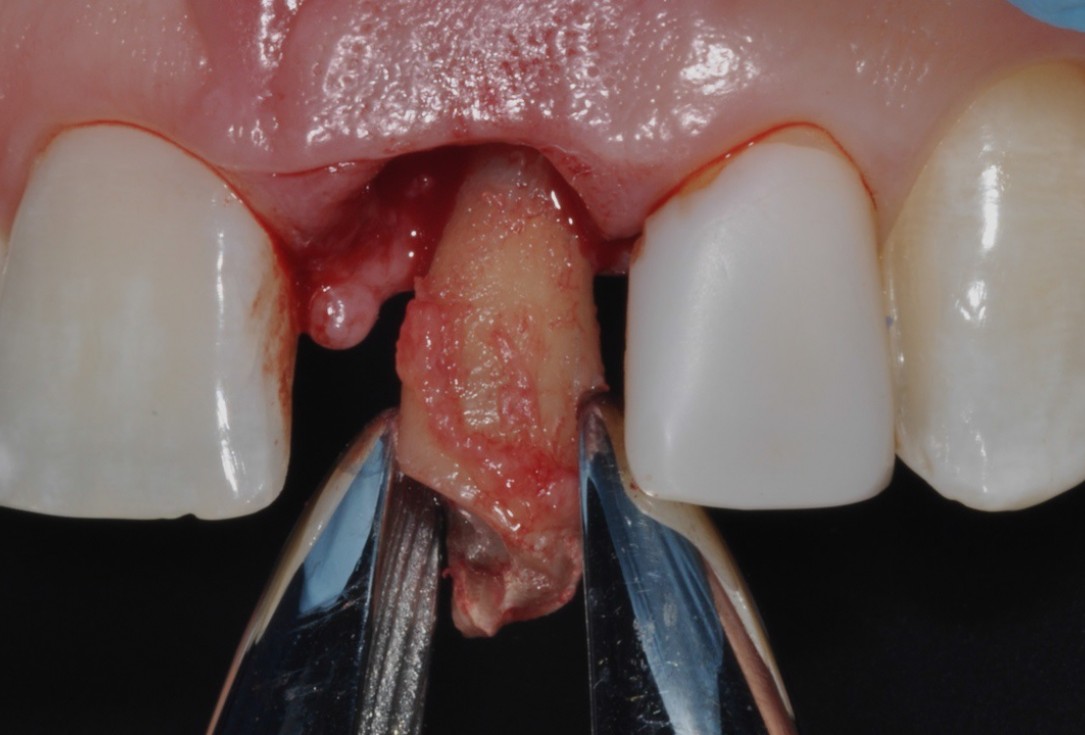

04/16 - Extraction of tooth root 21

Socket preservation with cerabone® - Dr. R. A. Nader